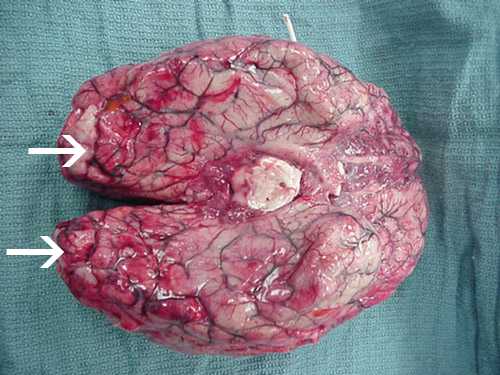

Photos of Naegleria fowleri

These photos of Naegleria fowleri in a variety of forms are presented to aid in laboratory diagnosis. Please be aware that these photographs are intended to aid in laboratory diagnosis and may be disturbing to some viewers.